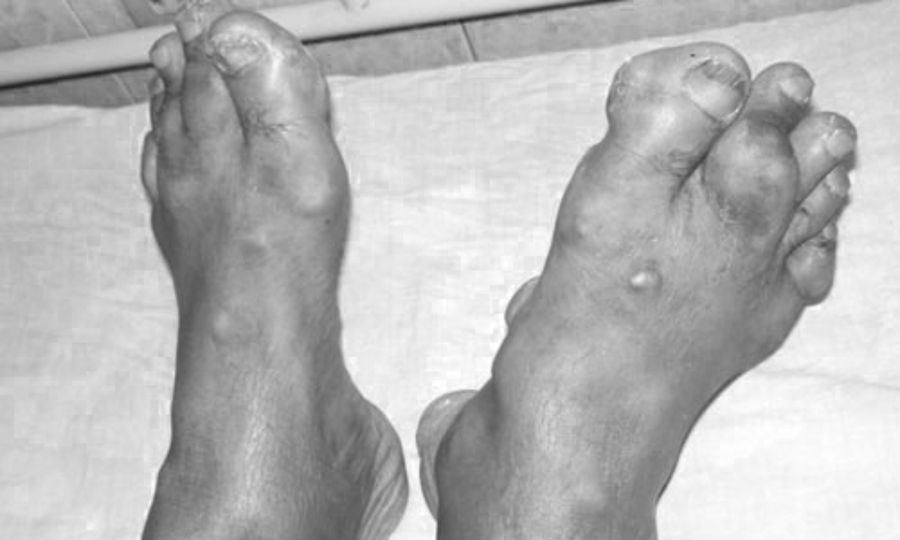

Các triệu chứng điển hình của cơn gút là đột ngột sưng, sốt và đỏ. , Đau khớp nghiêm trọng. Nếu không điều trị đúng cách, lâu ngày bệnh sẽ phát triển thành thoái hóa khớp, kèm theo thường xuyên đau nhức khớp, sưng tấy, biến dạng khớp, hạt tophi, bệnh thận, sỏi thận …- BS Ngọc khuyến cáo một lần. Đối với các khớp bị sưng đau, người bệnh nên chủ động đến các cơ sở y tế để được khám và điều trị đúng cách. Không nên tự ý điều trị và ngưng điều trị khiến tình trạng bệnh ngày càng trầm trọng hơn. Ngoài việc sử dụng thuốc, người bệnh cũng nên có chế độ ăn uống, sinh hoạt và tập luyện hợp lý. Uống nhiều nước, bỏ thuốc lá, rượu bia, tránh ăn thức ăn giàu đạm động vật như nội tạng động vật, thịt bò, hải sản … Tập thể dục thường xuyên và duy trì cân nặng phù hợp có thể cải thiện đời sống tình dục. Bác sĩ Ngọc khẳng định: “Bệnh gút không phải là bệnh nan y, bệnh nhân hãy kiên trì và làm theo hướng dẫn của bác sĩ thì chắc chắn sẽ khỏi bệnh.”